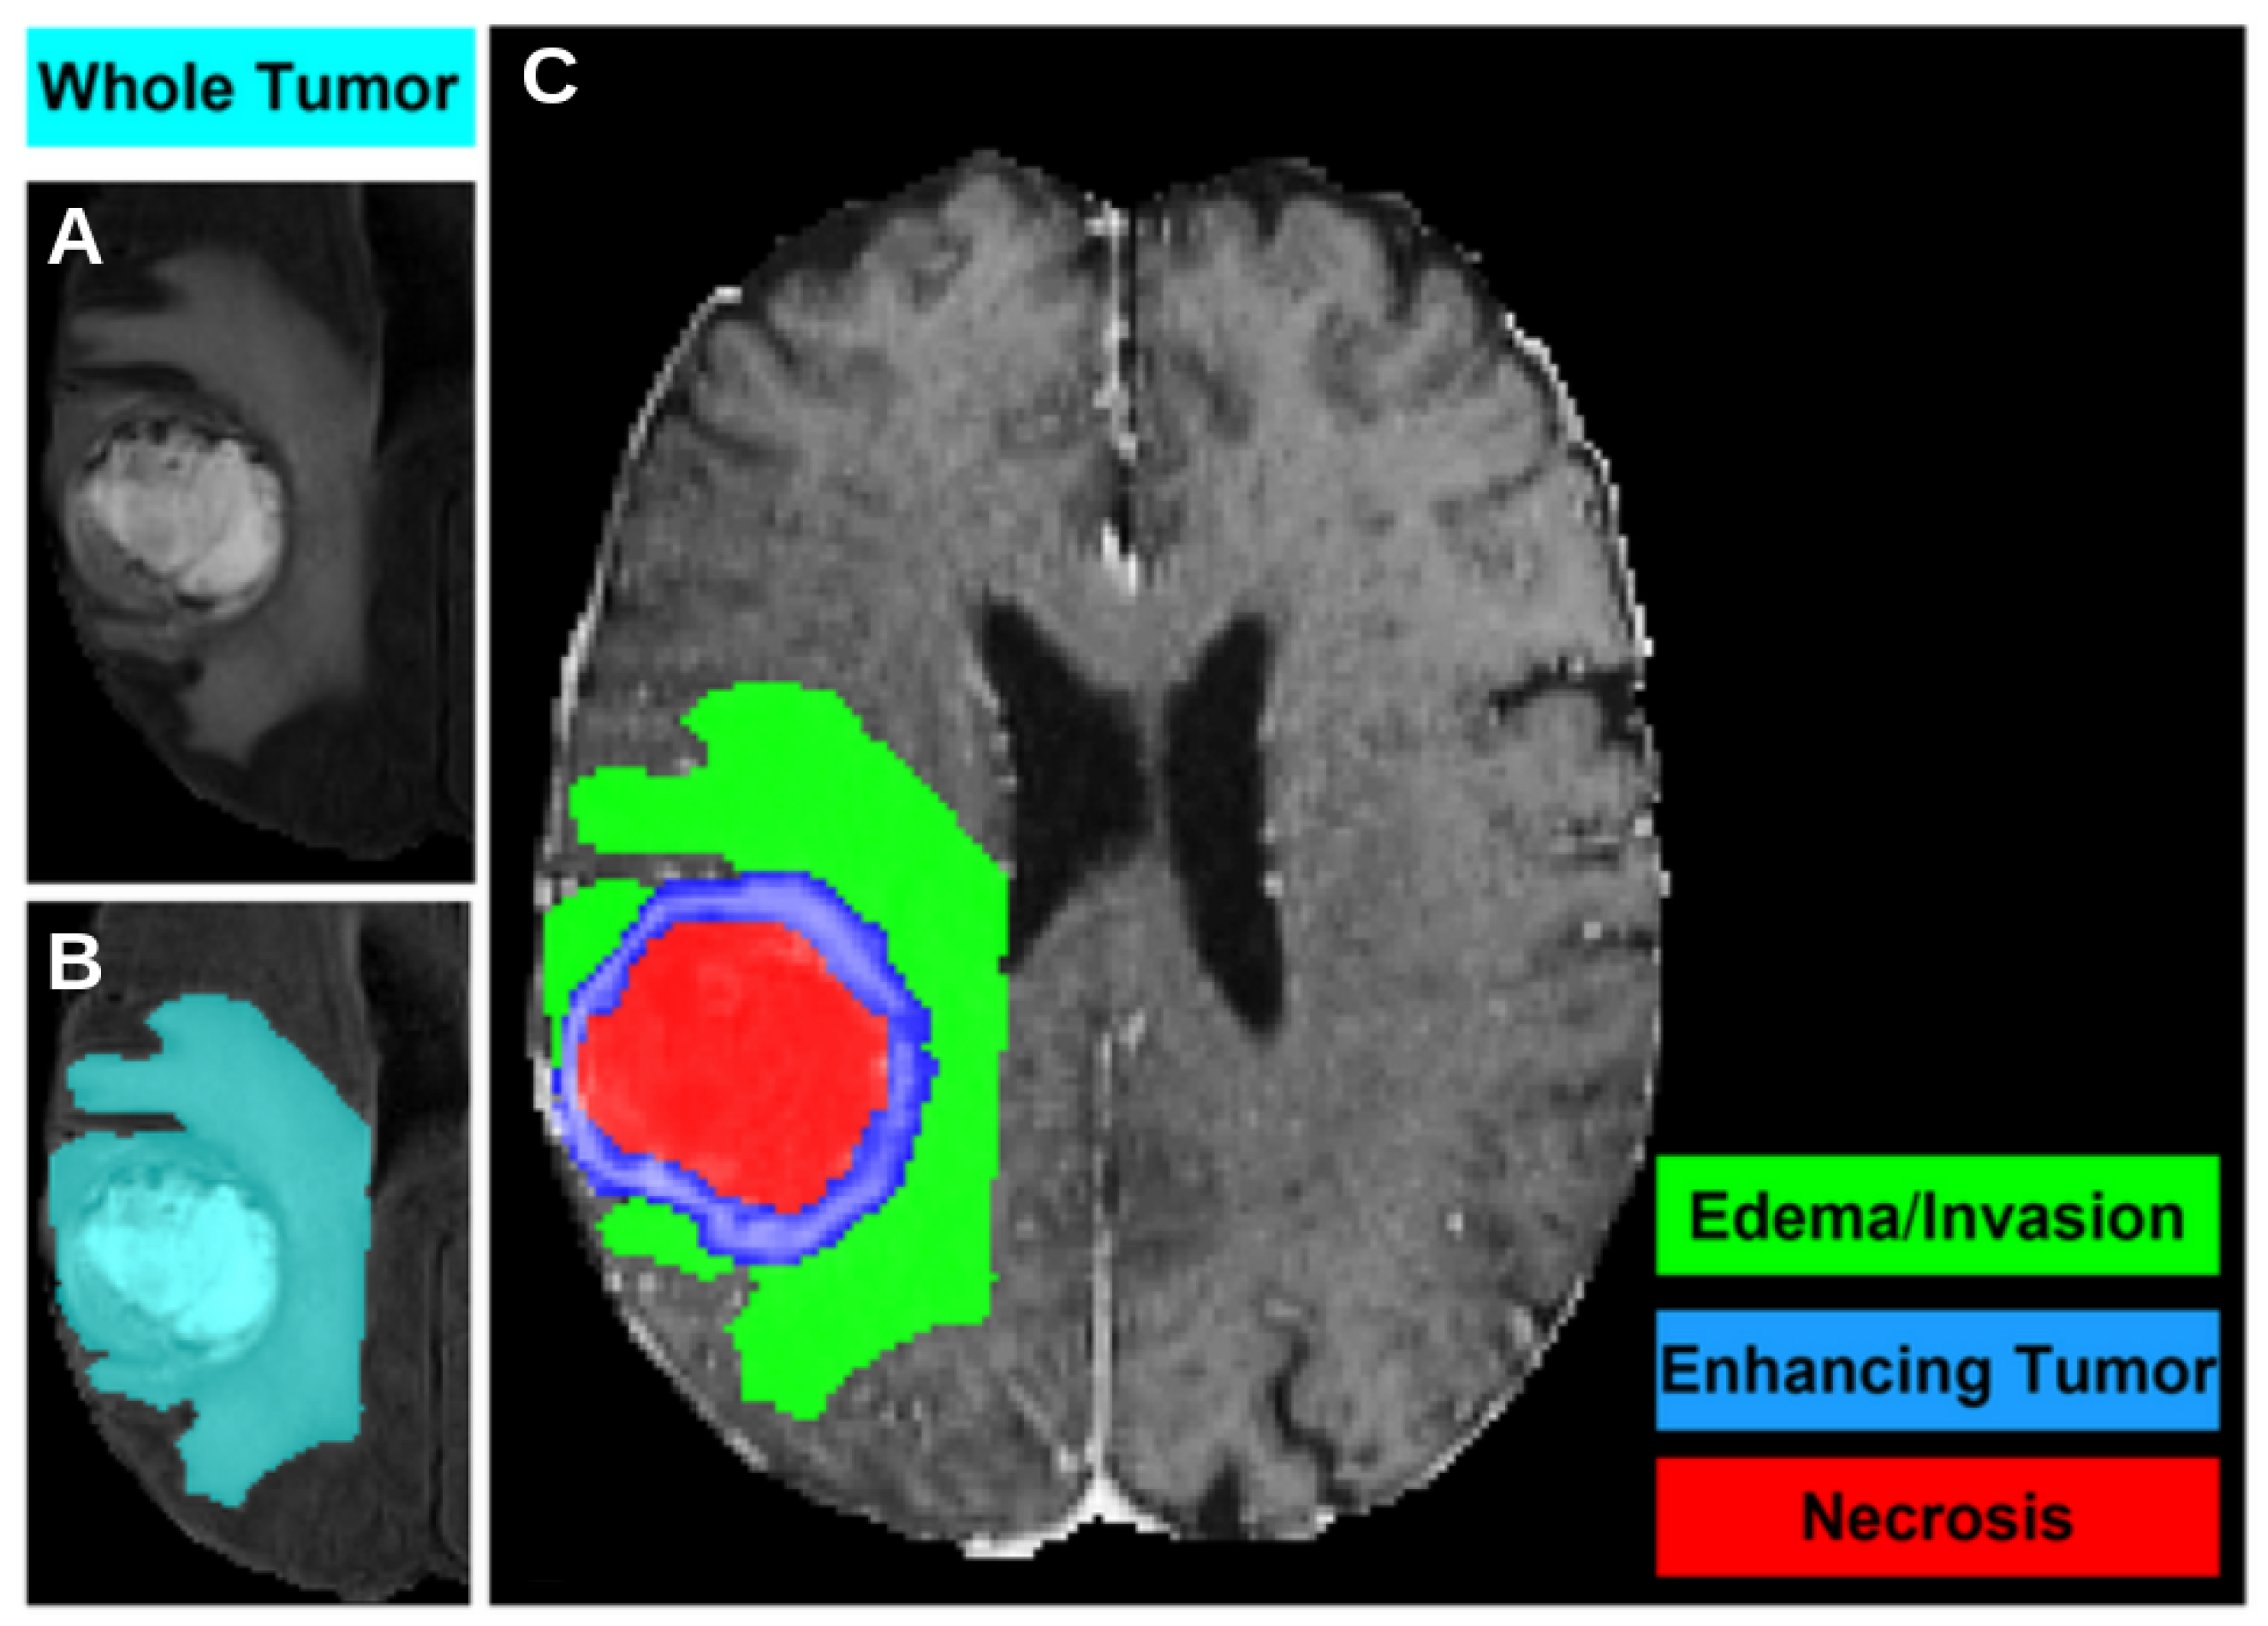

All images were pre-processed using a standardized protocol that included the coregistration of all mpMRI scans to a common anatomical atlas, resampling to an isotropic resolution of 1 , and skull-stripping. Each patient had pre-operative images in four modalities (T1, T1-contrast enhanced, T2, and FLAIR) along with Diffusion Tensor Images (DTI), including the Fractional Anisotropy (FA) and the Axial Diffusivity (AD) maps that are exploited in this study. Two different types of segmentations are available. The first segmentation was performed using the STAPLE label fusion technique [14], which combines the results of three top-ranked deep learning algorithms from the BraTS challenge: DeepMedic, DeepSCAN, and nnUNet. The second segmentation is a manual revision and correction of the first, conducted by expert clinicians for a subset of 232 subjects. The output of the segmentation delineates different masks, highlighting various parts of the tumor: the enhancing part of the tumor core (ET), the non-enhancing part of the tumor core (NET), and the peritumoral edema (ED). These are illustrated for a representative subject of the dataset in Figure 1.

Figure 1.

An axial slice of a T1-weighted MRI of the dataset, where the different segmentation masks are visible: (A) the tumor, including all sub-portions, is shown in the original image grayscale; (B) the Whole Tumor mask, i.e., the union of the three previous masks, is shown in cyan; (C) the necrosis area is shown in red, the enhanced part of the tumor in blue, the edema in green.